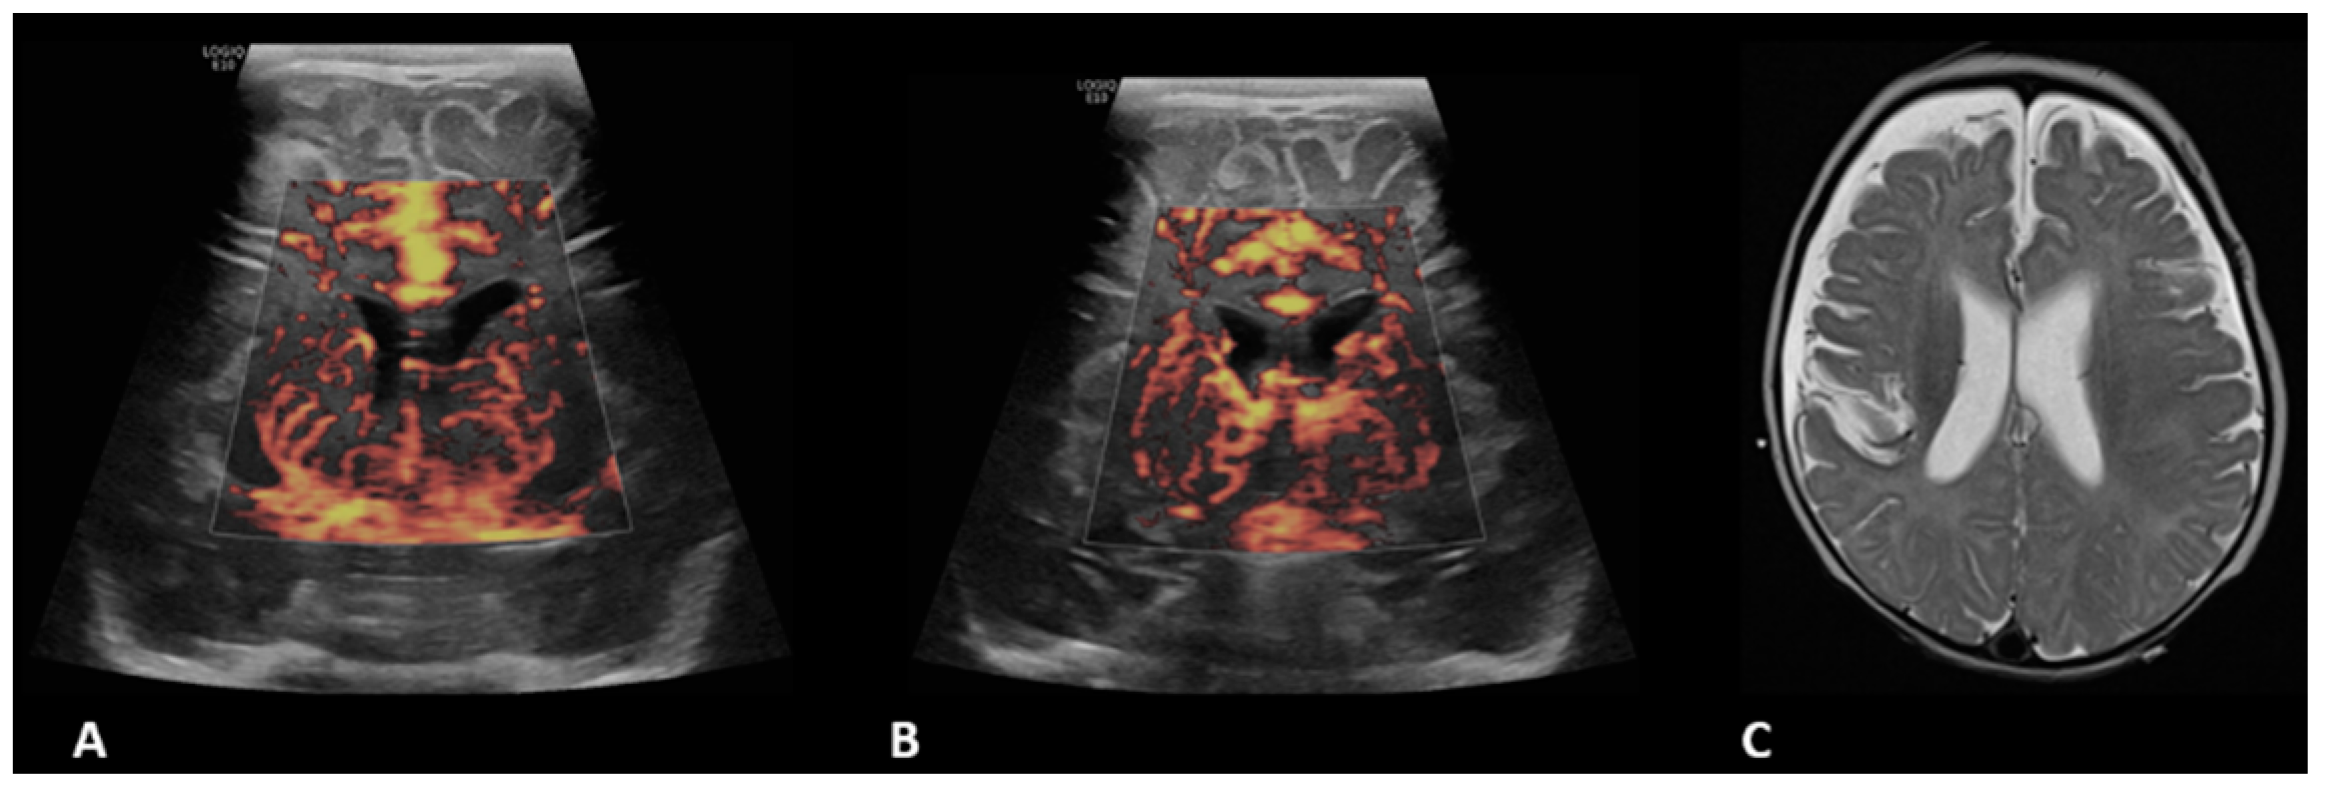

- Hwang, M.; Haddad, S.; Tierradentro-Garcia, L.O.; Alves, C.A.; Taylor, G.A.; Darge, K. Current understanding and future potential applications of cerebral microvascular imaging in infants. Br. J. Radiol. 2022, 95, 20211051. [Google Scholar] [CrossRef] [PubMed]

- Barletta, A.; Balbi, M.; Surace, A.; Caroli, A.; Radaelli, S.; Musto, F.; Saruggia, M.; Mangili, G.; Gerevini, S.; Sironi, S. Cerebral superb microvascular imaging in preterm neonates: In vivo evaluation of thalamic, striatal, and extrastriatal angioarchitecture. Neuroradiology 2021, 63, 1103–1112. [Google Scholar] [CrossRef]

- Goeral, K.; Hojreh, A.; Kasprian, G.; Klebermass-Schrehof, K.; Weber, M.; Mitter, C.; Berger, A.; Prayer, D.; Brugger, P.C.; Vergesslich-Rothschild, K.; et al. Microvessel ultrasound of neonatal brain parenchyma: Feasibility, reproducibility, and normal imaging features by superb microvascular imaging (SMI). Eur. Radiol. 2019, 29, 2127–2136. [Google Scholar] [CrossRef] [PubMed]